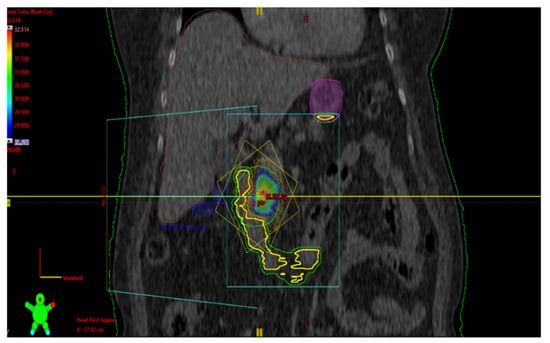

2. First Case